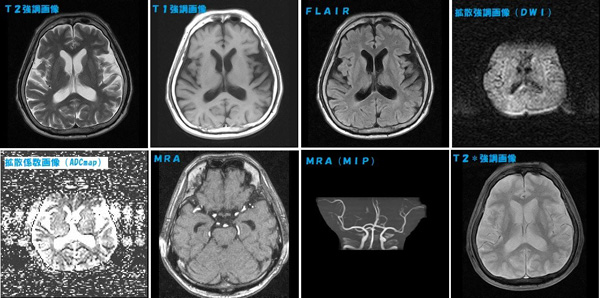

本棚にしまっていましたが使用しないので出品します。書き込みありません。非裁断です。「脳MRI 3 血管障害・腫瘍・感染症・他」高橋 昭喜定価: ¥ 12000#高橋昭喜 #高橋_昭喜 #本 #自然/医療・薬学・健康